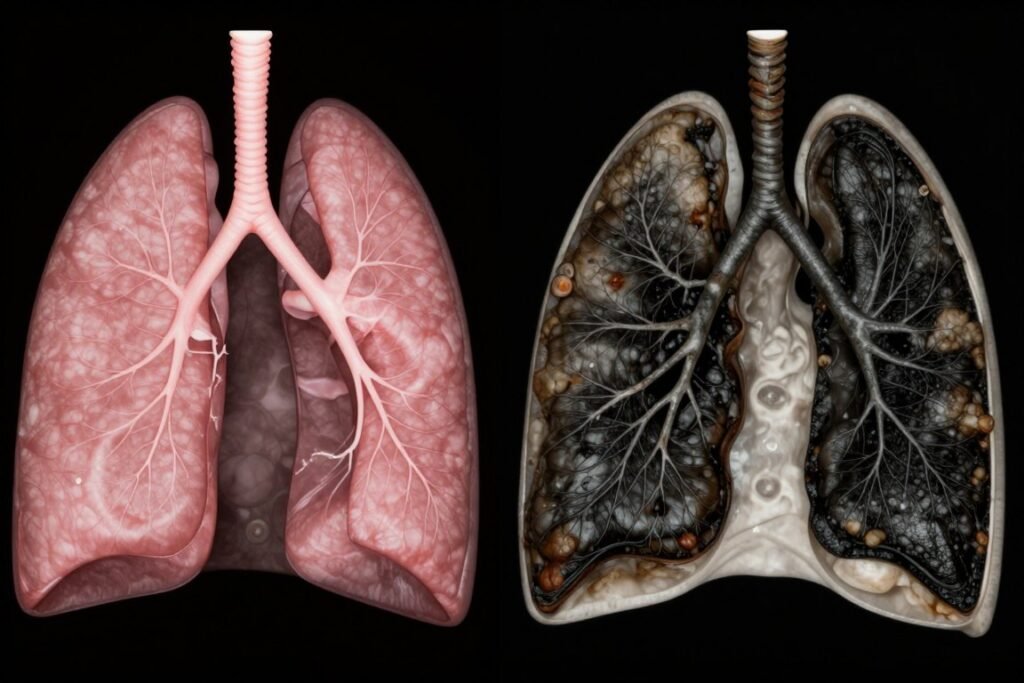

How COPD Affects Your Lungs

In healthy lungs, air flows freely through airways into air sacs. These delicate structures facilitate oxygen exchange with the bloodstream.

COPD damages this intricate system. Airways become inflamed and narrowed while air sacs lose their ability to expand and contract properly.

The result is trapped air in the lungs. This phenomenon makes it increasingly difficult to breathe out completely.

COPD is a chronic, progressive condition. The lung damage characteristic of emphysema chronic bronchitis cannot be completely reversed.

Permanent structural changes occur in airways and air sacs. Once these delicate structures are damaged, they cannot regenerate to normal function.

This differs fundamentally from reversible conditions like asthma. While asthma involves temporary airway narrowing, COPD causes permanent tissue damage.